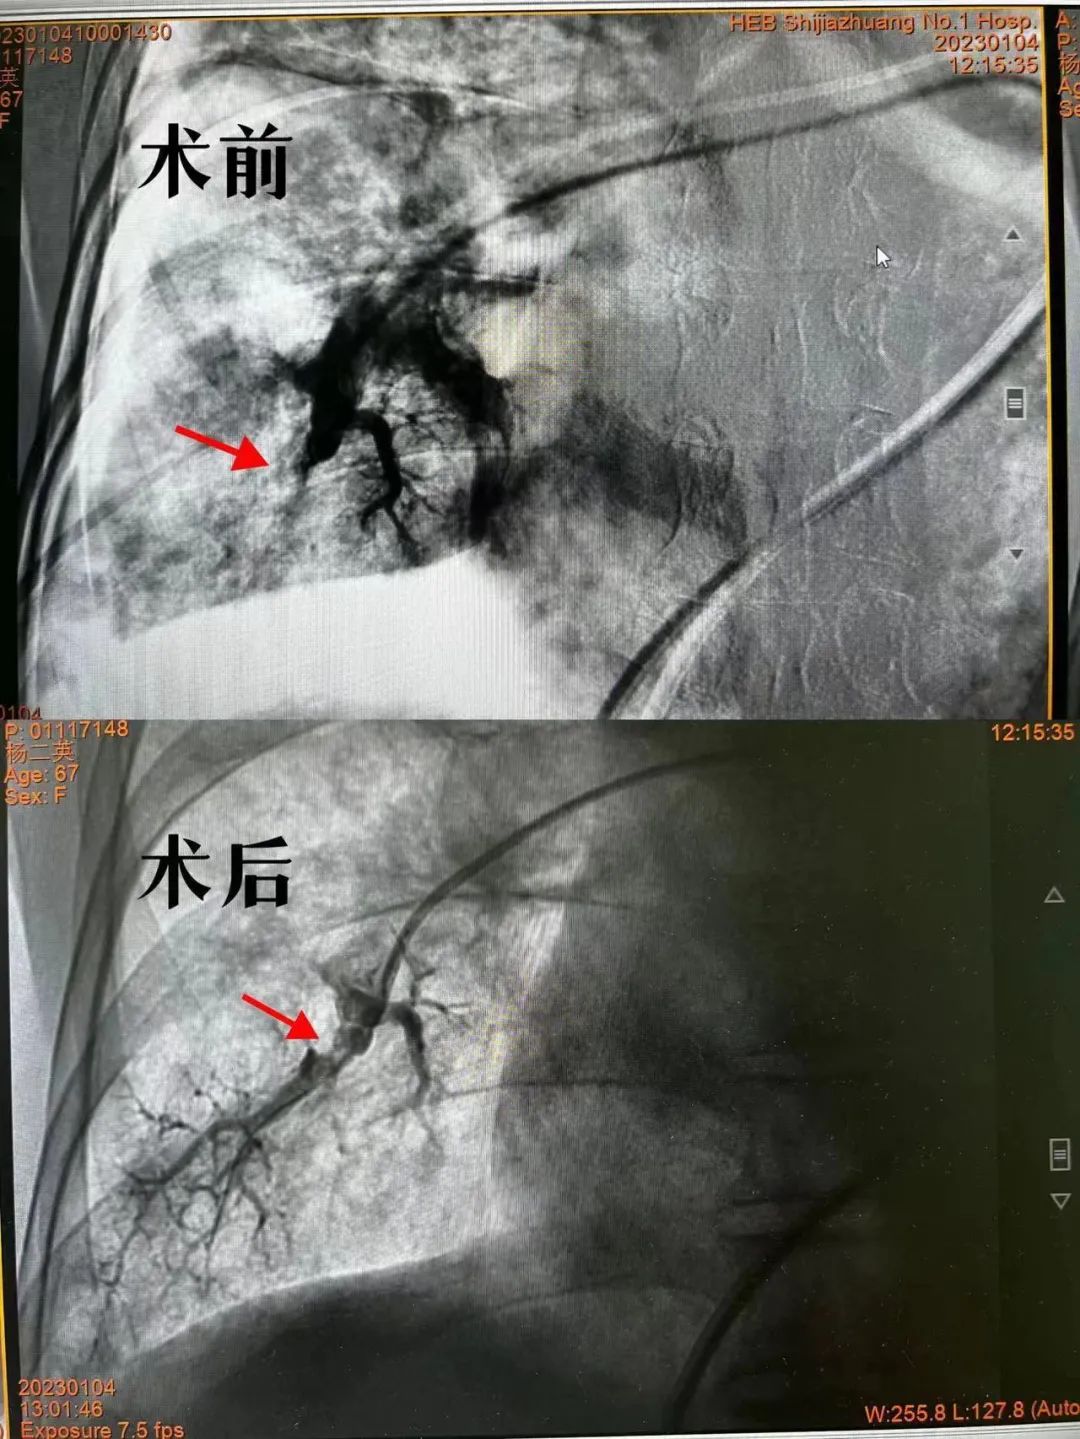

在与患者及家属沟通、完善各项准备工作后,米杰副院长、心血管内一科刘东超医生为患者行肺动脉造影,显示右肺动脉多个分支闭塞,病情严重。当前迫在眉睫的是要开通堵塞的血管,赢得生机。术中,经导丝将球囊“长途跋涉”送至肺动脉,撑开狭窄及堵塞处,每一步操作都一丝不苟、沉稳专业。终于,两根右下肺动脉的血管开通了,血运重建成功!

术前,患者吸着氧气,指脉氧88%。术后,不吸氧气的情形下,指脉氧达到了95%。不适症状缓解。目前,患者已出院,开启了新的生活。